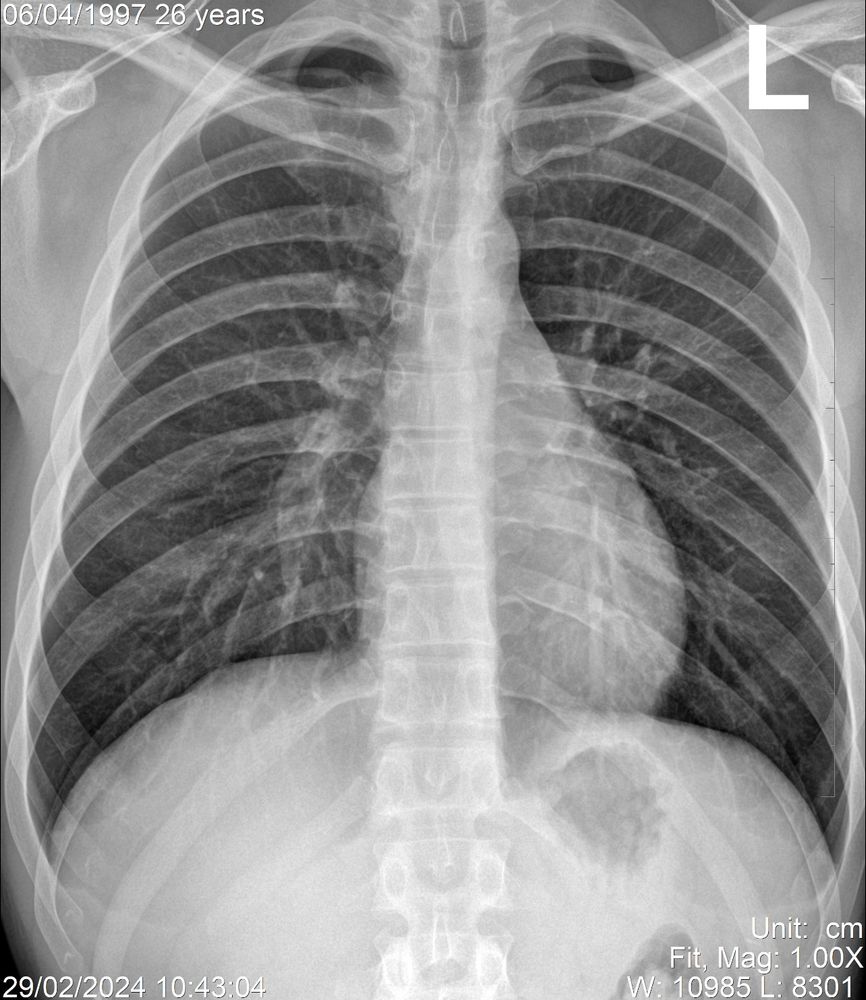

Ячеистая деформация легочного рисунка: медицинская визуализация